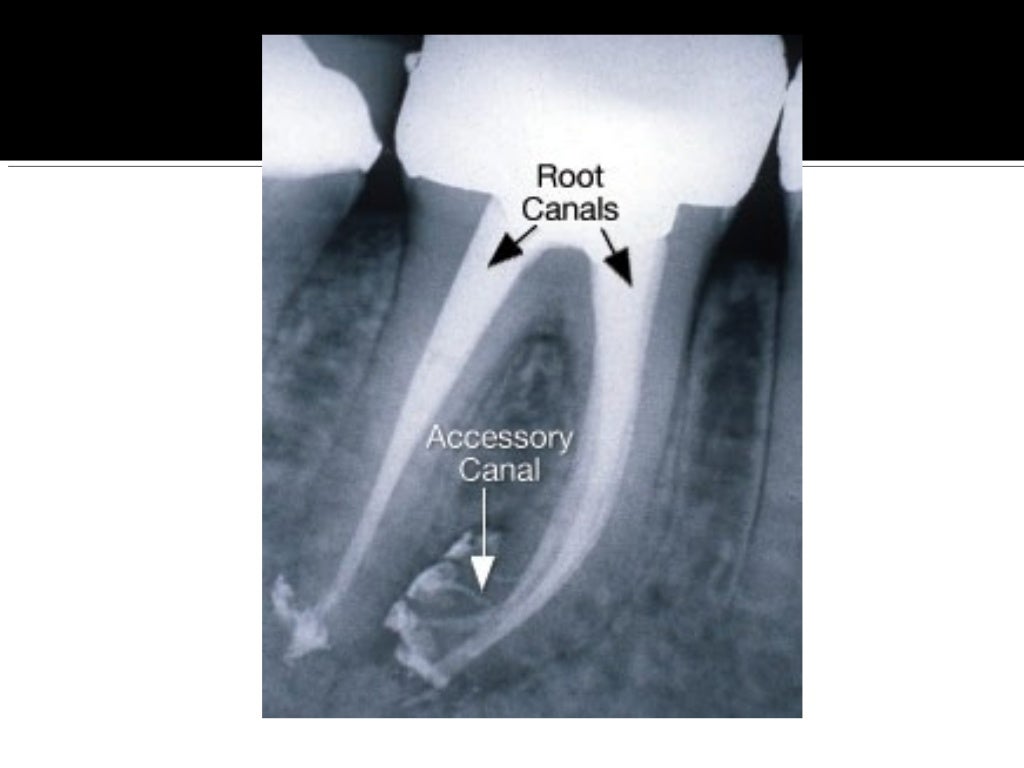

From www.slideshare.net

Root canal anatomy and access cavities What Is A Calcified Root Canal what are calcified root canals? This condition is better known as. what is a calcified tooth? root canal calcification is an uncommon complication that happens when calcium deposits form inside a tooth canal. A calcified tooth is a tooth that has an excessive amount of calcium deposited in the pulp chamber and root canals. Successful root canal. What Is A Calcified Root Canal.